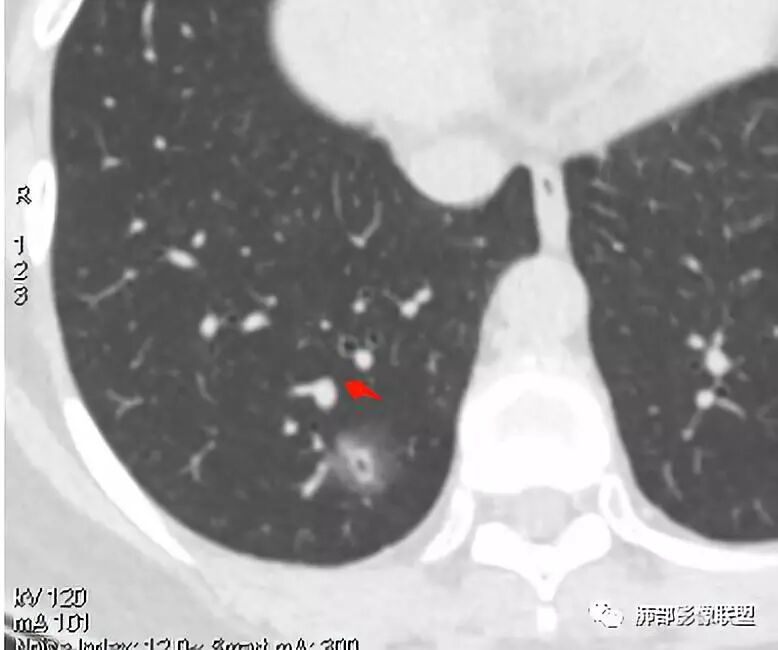

连续层面显示这个应该是空泡,或者小空洞,远端没有,近端也没有,周围环形软组织增厚。而空泡,影像上只是根据5mm界线,病理上不一定。

南边:

这些呢?为啥?

动脉,有支气管伴行

伴有支气管

假如这是含气支气管,伴随的哪条动脉呢?近端从哪来?为啥环形壁增厚而又不均匀?都不太符合,所以支持空泡或小空洞。

上次刘纯老师提出,空泡征是一个影像征象,不是一个病理征象,我比较支持,他就是一个影像上的小低密度腔,原因很多,但是影像上与小的空洞表现区分不了。其中的原理:有一条是内容物排出后的残腔,其实也是空洞的原理。

大家考虑恶性的依据?炎性的依据?首先这是不是磨玻璃结节?依据是啥?

因为密度比肺组织高,但是又遮盖不了血管,所以GGO明确

是pGGO?mGGO?

实性的部分超过10%——mGGO